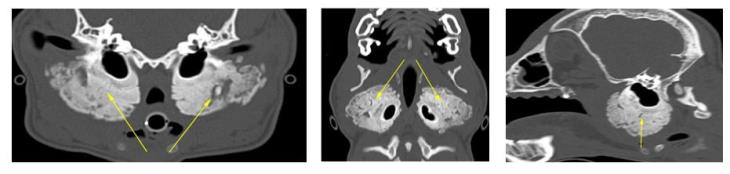

A 6-month-old West Highland White Terrier was referred to our hospital due to severe oral pain and the impossibility to open his mouth. A CT scan was performed and a severe, bilateral and symmetric ‘palisading’ periosteal reaction, was observed at the level of the temporal bones (yellow arrows). The temporomandibular joints and the tympanic bullae were within normal limits.

A diagnosis of craniomandibular osteopathy was made; an autosomal recessive, self-limiting developmental disease, primarily seen in Highland terriers.

A 3D reconstruction of the head is also displayed below, with the lesion highlighted by green arrowheads.